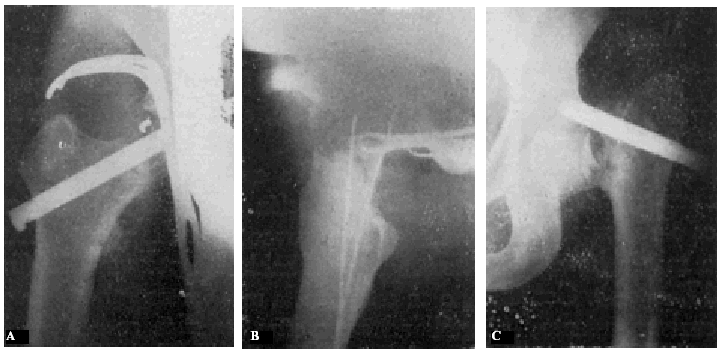

Con buena técnica, todos los resultados son favorables, a pesar de que al cabo de algunos años exista un grado más o menos acentuado de artrosis (véanse la observación núm. 4, fig. 7., A y B, y la observación núm. 9, fig., 8. A, B y C), que corresponden a los dos enfermos que hace más tiempo que están operados, y que en la actualidad aún viven.

Figura 7. A: obs. núm. 4. Enfermo de sesenta y cuatro años, operado en noviembre de 1935. La situación del clavo puede aceptarse como buena (ligeramente craneal). B: obs. núm. 4. Radiografía del mismo enfermo de las dos figuras anteriores, practicada en la actualidad (julio de 1943). Artrosis manifiesta. La cabeza del fémur tiende a aplastarse. Deambulación perfecta.

Figura 8. A: obs. núm. 9. Enferma de cuarenta y cinco años, operada en enero de 1937. El clavo procedía del cadáver de la observación mencionada como fracaso número I, y presentaba unos ligeros depósitos de herrumbre. La situación del clavo es buena. B: obs. núm. 9. El mismo caso de la figura anterior. En proyección lateral también es perfecta la situación del clavo. Éste tuvo que ser extraído a los siete meses de intervenida la fractura, a causa de una persistente supuración. C: obs. núm. 9. Radiografía del caso de las dos figuras anteriores, practicada en julio de 1943. Artrosis muy ligera. El cuello del fémur parece muy estrechado, pero esta deformidad también puede apreciarse en la figura B. Deambulación perfecta.

No consideramos como un fracaso el tener que sacar el clavo, maniobra que hemos practicado en tres casos (en la obs. núm. 9, fig. 8., A, B y C; la núm. 30, C y D, y núm. 18, fig. 17, A y B) que hemos citado anteriormente, en el cual la extracción provocó el exitus letalis.

Muchos fracasos de Böhler se deben a haber cargado precozmente la extremidad. La figura 15, A y B8, corresponde a un fracturado operado por Böhler. El clavo está bien colocado en las dos proyecciones, aunque es poco profundo y ligeramente ventral en lugar de dorsal. A los dos meses, cuando el enfermo andaba perfectamente bien, nota el enfermo bruscamente dolores y se comprueba a la exploración radiográfica que el clavo se había salido de la cabeza del fémur (fig. 15, C y D). Dice Böhler, referente a este caso: «Este desprendimiento no habría ocurrido si el clavo se hubiera colocado algo más caudal y más dorsal respecto a la línea media del cuello y de la cabeza y, a la vez, hubiese penetrado lo suficiente en ésta». Y añadimos nosotros: a pesar de que la situación del clavo no era idealmente perfecta en este caso, la culpa del fracaso reside fundamentalmente en la carga precoz del miembro fracturado. Si observamos la figura 16, A y B (observación núm. 23), aunque en proyección anteroposterior, la situación del clavo puede considerarse perfecta; en proyección lateral, está en situación mucho más ventral que la observación anterior de Böhler, y sin embargo la enferma, operada en mayo de 1941, anda en la actualidad, a pesar de sus setenta y ocho años, sin la ayuda de ningún bastón y sin presentar ninguna molestia (fig. 16 C). La situación del clavo en este caso es muy semejante a la de la enferma citada anteriormente, que falleció al extraerle el clavo intolerante (supuración de la herida, sin síntomas generales de infección) (fig. 17 A y B; obs. núm. 18), por lo que todo hace suponer que, en caso de no haberse presentado el desenlace fatal, el resultado funcional hubiera sido bueno.

Figura 16. A: obs. núm. 23. La situación del clavo en esta proyección es buena. B: obs. núm. 23. El mismo caso de la figura anterior, en proyección lateral. La situación del clavo es excesivamente ventral. C: Obs. núm. 23. El mismo caso de la figura anterior, en la actualidad. A pesar de la artro-sis existente, la enferma no presenta la más mínima molestia ni se halla limitada la movilidad articular.

Figura 17. obs. núm. 18. La fractura está enclavada en valgus. El clavo está bien colocado, aunque es algo corto. B: obs. núm. 18. El mismo caso de la figura anterior, en posición lateral. El clavo, algo corto, está colocado en la misma posición defectuosa que el caso de la figura 16, B.